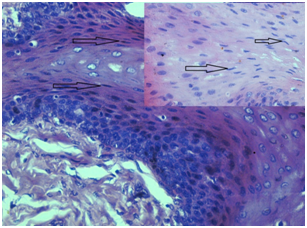

Under Normal circumstances cells will be maintaining a state of homeostasis. When there is any change in the environment, cell may adapt to the new environment. But, when deleterious stimulus is severe, it will lead to irreversible injury of cell. Cell death may occur due to various causes which include hypoxia, ischemia, toxins, immune reaction etc.4 Morphological and biochemical change in the cell varies in different causes of death which we expected to observe histologically. Within our study in the hypoxic death, cells appeared to be swollen and cell membrane as well as nuclear membrane was distinct (Figure 1). As the energy dependent sodium pump function of plasma membrane is reduced due to ATP depletion, there will be intracellular accumulation of sodium and diffusion of potassium out of the cell. When oxygen supply to cell is reduced, cells oxidative phosphorylation ceases and cell relies on glycolysis for energy production. Mitochondria in cell are affected in all types of injury, and can be damaged by increased cytosolic Ca2+. In hypoxic death increased Ca2+ results in activation of various autolytic enzymes like ATPase, phospholipase etc., which has deleterious effects on cell. There will be early damage to lysosome membrane which results in leakage of lysosomal enzymes into cytoplasm and activation of enzymes such as ribonucleases, deoxyribonucleases etc. leading to enzymatic digestion of cell components.4,6 These changes were noted in our study as nuclear and cytoplasmic vacuolation (Figure 1).

Figure 1 (20x) Inside (40x) in hypoxic death cells appeared to be swollen and cell membrane as well as nuclear membrane was discernible.

Similar changes like nuclear and cytoplasmic vacuolation, loss of cell membrane were noted in histotoxic death. In addition to these changes in cases of histotoxic death we also noted arc and spindled shaped nucleus without vacuolation (Figure 2).

Figure 2 (10x) Inside (40x) in Histotoxic death cell showed arc and spindled shaped nucleus with or without vacuolation.